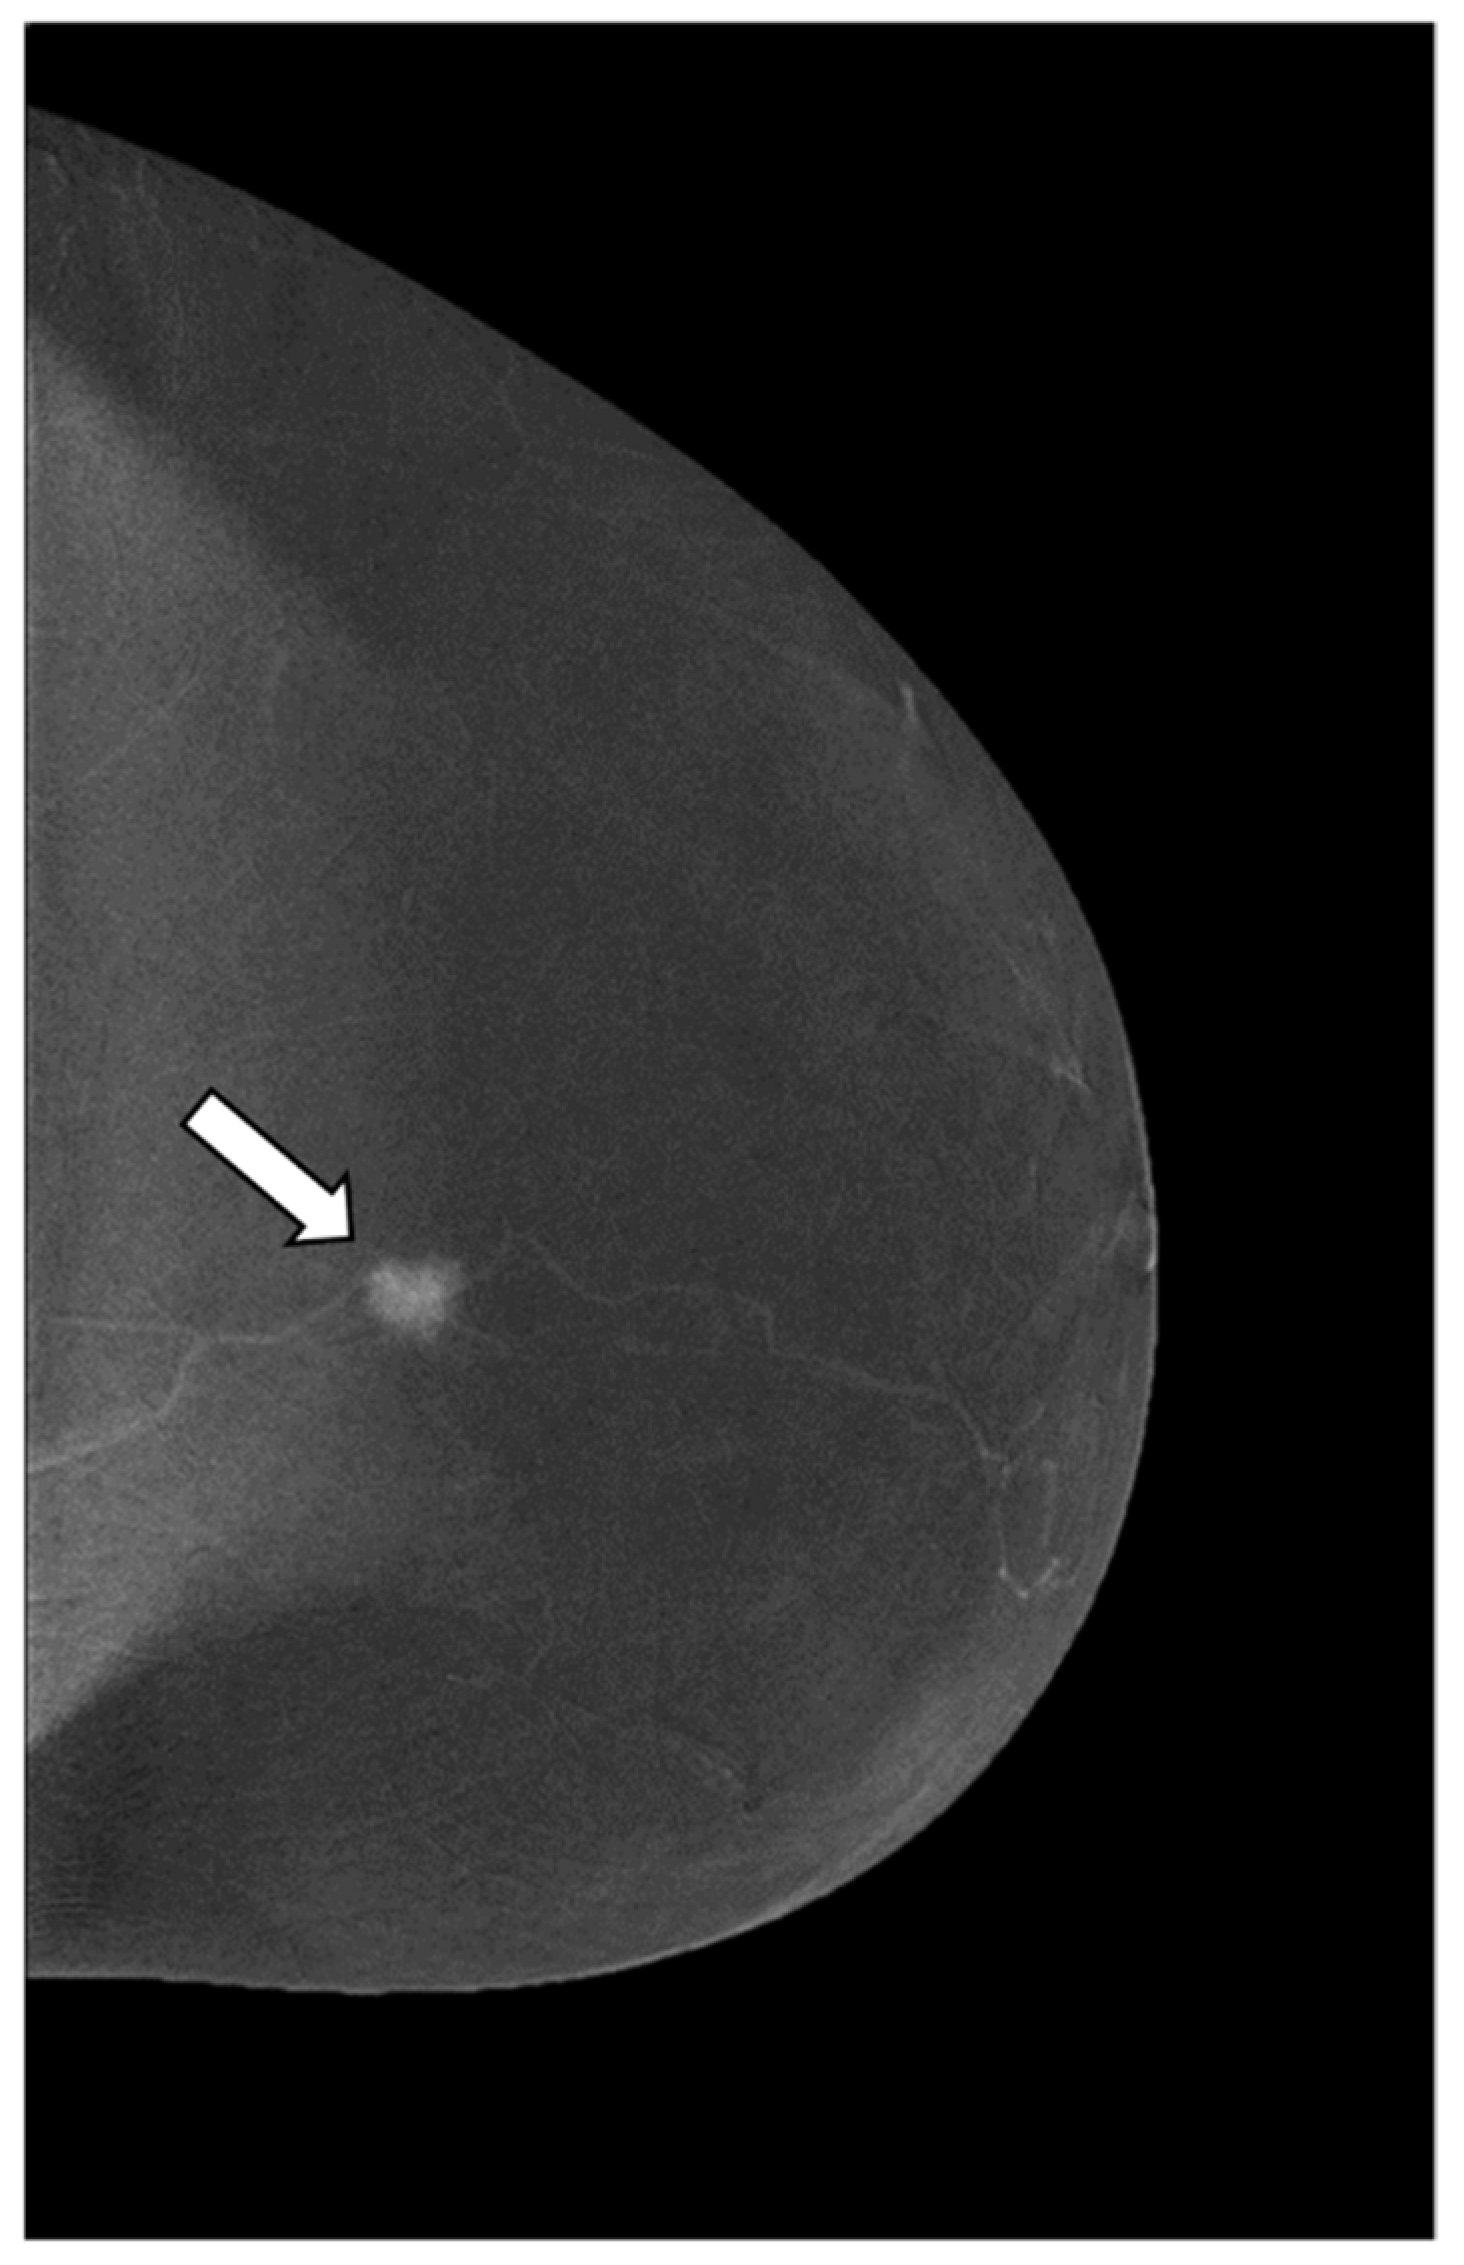

A Score to Predict the Malignancy of a Breast Lesion Based on Different Contrast Enhancement Patterns in Contrast-Enhanced Spectral Mammography